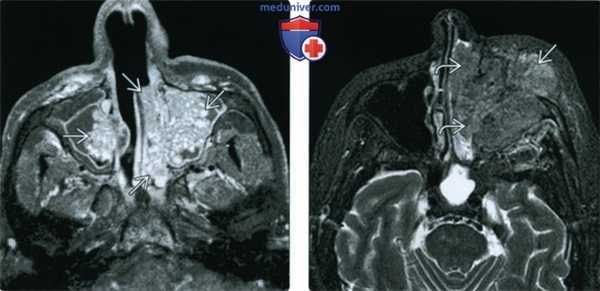

(Слева) При аксиальной МРТ Т1 С+ в верхнечелюстных пазухах визуализируются нетипичные (вследствие трансептального распространения) инвертированные папилломы с обеих сторон. Наибольшая опухоль с левой стороны заполняет полость носа. Обе опухоли внешне напоминают кору мозга.

(Справа) При аксиальной МРТ STIR визуализируется плоскоклеточная карцинома, возникшая в инвертированной папилломе полости носа слева В и левой верхнечелюстной пазухи. Карцинома разрушает переднюю стенку верхнечелюстной пазухи и распространяется в предчелюстные мягкие ткани.